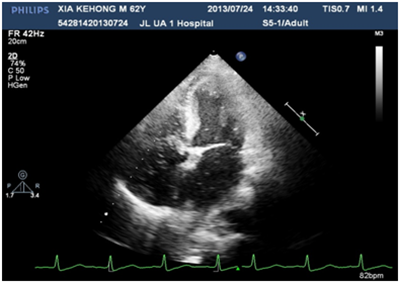

A 60years old male, known case of diabetes mellitus, hypertension and alcoholic hepatic cirrhosis had exercise induced chest discomfot, shortness of breath, fatigue and lips cyanosis half a year ago, which relieved at rest. But later he became serious for one week and visited our department for further management. He had no cough, fever, dizziness, headache or bleeding history from any site. He had pituitary adenoma, which was surgically removed 6years ago. He denies history of chronic infections such as tuberculosis or actinomycosis or family history of hereditary hemorrhagic telangiectasis (HHT). Physical examination revealed cyanosis of the face and lips, clubbing, numerous spider naevi on neck, chest and palm and no telangiectasia on mucosa or fundi. His blood pressure was 130/80mmHg, heart rate was 76beats/min and resting oxygen saturation was 66% in room air. A grade 1/6 soft systolic murmur was heard on the upper left sternal border and clear lungs sound. There were no bruits. The hemoglobin was 11.5gm/dL and the hematocrite was 35.5gm/dL. Arterial blood gas analysis showed Pao2 64mmHg on room air and after 100% of oxygen 74mmHg with Paco2 41mmHg and PH-7.35. Chest radiography and electrocardiogram did not show any abnormalities. Pulmonary function test showed alveolar dispersion function severely reduced. Transthoracic echocardiography showed normal findings (No PFO/ASD/VSD/PDA detected). We performed contrast echocardiography using agitated saline. A delayed appearance of a substantial amount of micro-bubbles in the left atrium greater than three cardiac cycles after appearance in the right atrium and ventricle (Figure 1) which was suggestive of pulmonary arteriovenous fistula. The delayed appearance and a large amount of micro-bubbles in the left atrium preclude the intracardiac shunting resulting from a patent foramen ovale (PFO) or arterial septal defect (ASD). Interestingly, the density of micro-bubbles was the same in the left and right cardiac chamber even after 10 cardiac cycles (Figure 2 & 3) and when the injection stopped, there were micro-bubbles in the left cardiac chambers meanwhile none in the right cardiac chambers (Figure 4). Because the hepatic function of the patient was in compensatory period, we gave him oxygen-inhalation and beta-blockers in order to decrease the oxygen demands and to lower the portal vein pressure. Moreover, he was advised to avoid sudden standing. The cyanosis improved, and the patient was discharged from the hospital and on regular follow-up. The patient was advised for pulmonary angiography but refused.

Figure 4 When the injection was stopped, there were micro-bubbles in the left cardiac chambers meanwhile none in the right cardiac chambers.